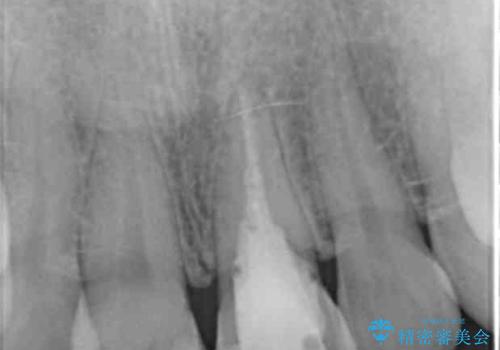

X線検査を行い診断的な小手術を行ったところ、歯に亀裂があり修復が不可能な状態であることがわかりました。

長期的な予後を見通すことが難しかったので、亀裂のある前歯の抜去を行いブリッジで審美性・機能性の回復を行いました。